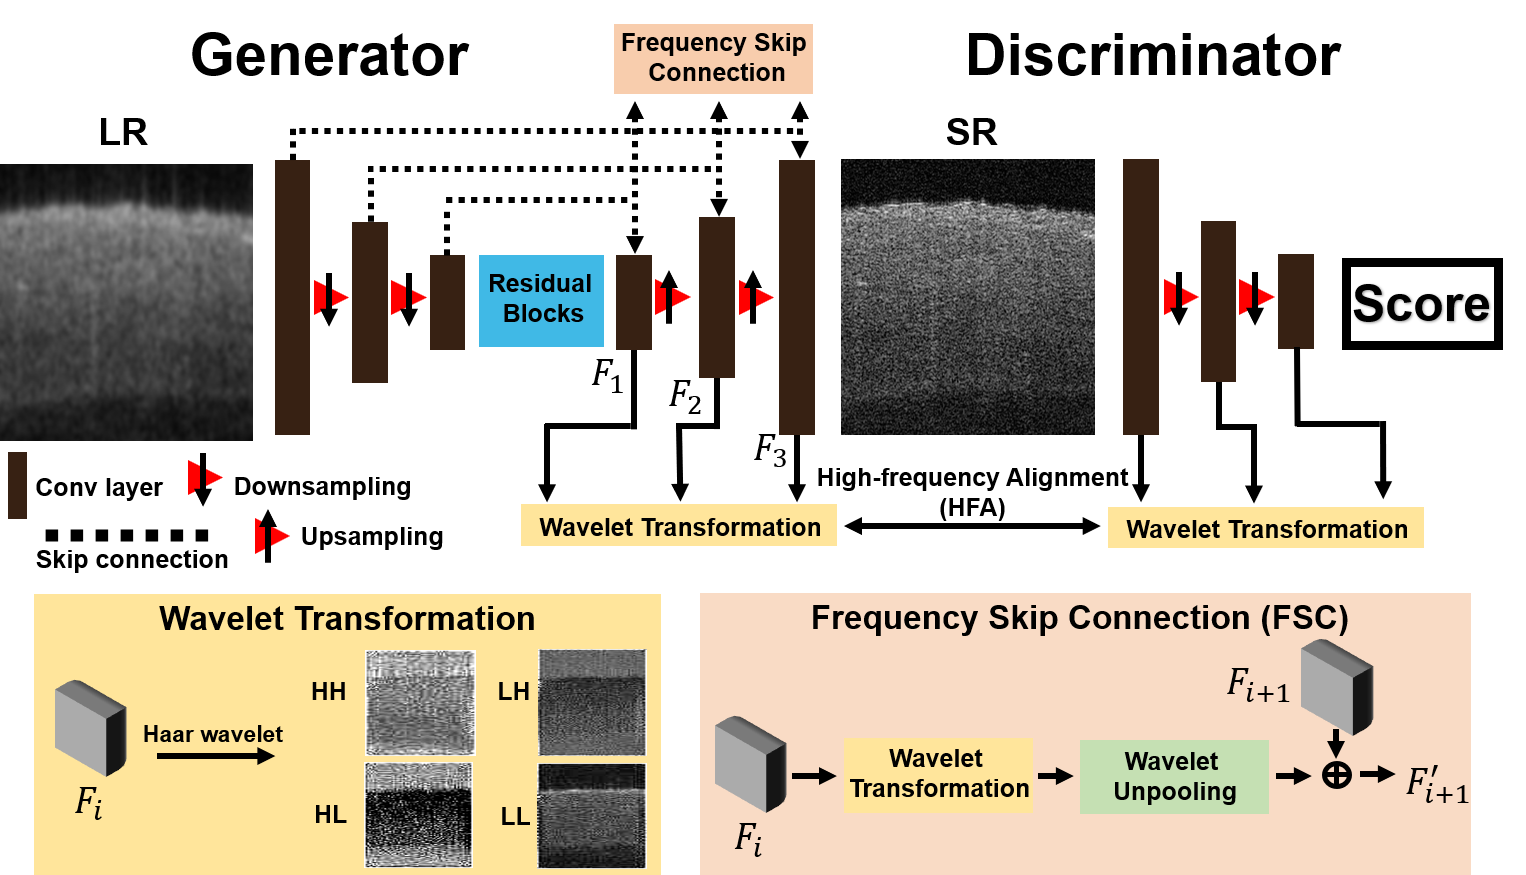

The design of our frequency-aware framework is shown in Fig 2. Our framework consists of a generator () and a discriminator (). Generator translates a LR image to a SR image. Discriminator classifies whether or not the generated image is realistic. Wavelet transformation is utilized to decompose feature maps into different frequency components; frequency skip connection (FSC) is used to prevent the loss of high-frequency information; high-frequency alignment (HFA) is used to guide the G for generating frequency information [29].

2.2.1 Wavelet transformation

We adopt Haar wavelet for decomposing feature maps of the -th layer into different components. Haar wavelet consists of two mirror operations: wavelet pooling and wavelet unpooling. The wavelet pooling converts images into the wavelet domain, and the wavelet unpooling inversely reconstructs frequency components into the spatial domain. During wavelet pooling, is convolved with four distinct filters: , , , and , where and are low and high pass filters respectively (, ). The low pass filter () provides general shapes and outlines in ; the high pass filters (, , ) provide more fine details such as segments, edges, and contrasts. An illustration of wavelet transformation is shown in Fig 2.

2.2.2 Frequency skip connection

To prevent the loss of high-frequency information from to , FSC is used in generator . The FSC in G is defined as:

| (1) |

After the frequency skip connection, feature map is calculated with the frequency information of is preserved through this process.

2.2.3 High-frequency alignment

High-frequency alignment (HFA) provides with a self-supervised learning scheme using frequency information acquired in . For in G, we acquire , , , and . The combination of high-frequency components in is defined by: . Similarly, high-frequency components in can be acquired by . The can be used as the self-supervision constraint to train .